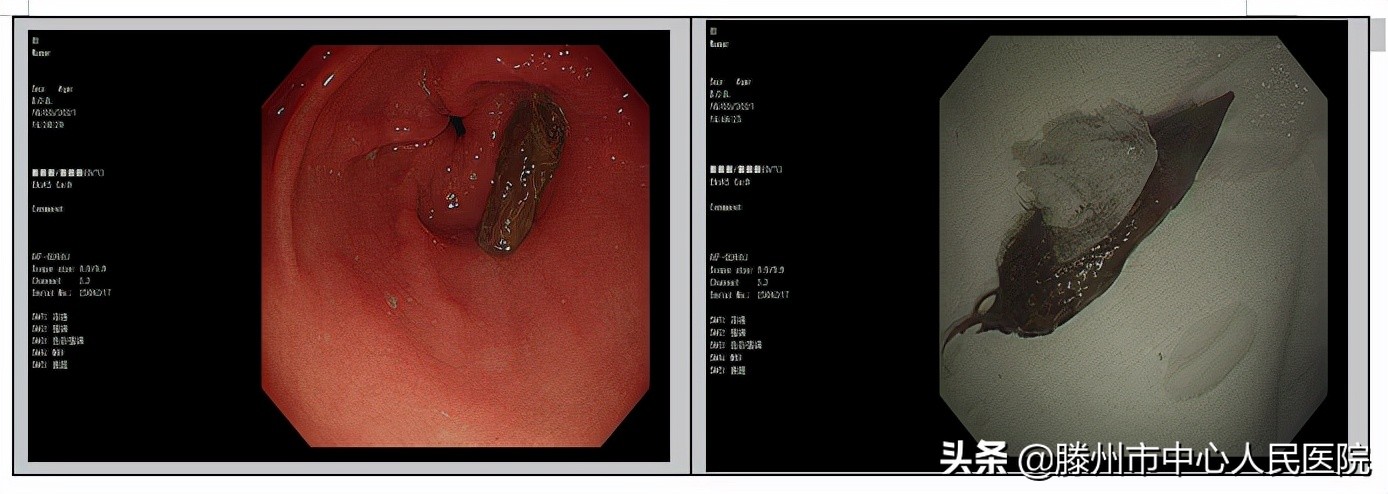

枣核